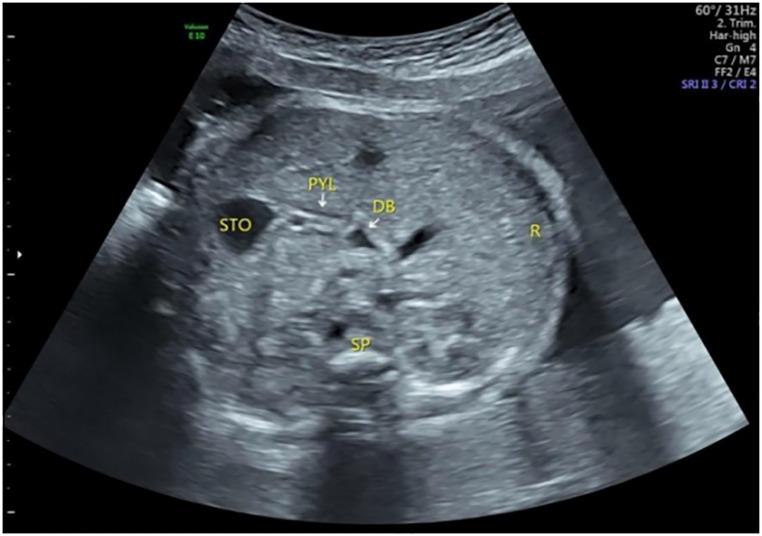

To use the fetal pylorus as a reference point to conveniently display the normal fetal duodenum by ultrasound.

This study was designed in cross-section. A total of 450 healthy singleton pregnant women at 19-39 weeks of gestation who underwent prenatal screening at our hospital from January 2019 to February 2020 were selected. They were divided into three groups according to gestational weeks: the 19-23 gestational weeks group, 29-32 gestational weeks group, and 34-39 gestational weeks group. The duodenal bulb was identified. Its movement and course were continuously and dynamically observed. The descending part of the duodenum was identified, and the duodenal course was traced.

The fluid-filled in the fetal duodenum was discontinuous. The overall detection rates of the duodenum in the 19-23 gestational weeks group, 29-32 gestational weeks group, and the 34-39 gestational weeks group were 82.2%, 26.2%, and 13.8%, respectively. The detection rates of the bulbar, descending, horizontal, and ascending parts of the duodenum were 94.4%, 58.2%, 58.0%, and 52.0%, respectively. The anatomical structures of the duodenum as a whole and the pancreas were most easily recognized in the 19-23 gestational weeks group; while in the 34-39 gestational weeks group, the bulbar part had a maximum detection rate of 98.8%, and it had the longest filling time and the shortest examination time.

The pylorus is an ideal starting point for tracing the fetal duodenum. The overall detection rate of the fetal duodenum decreases with gestational age. The duodenal bulb is the most easily detected site.